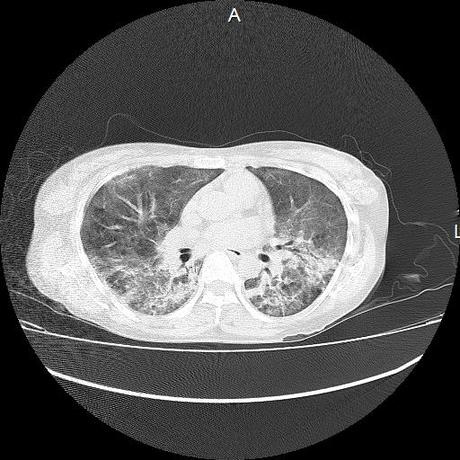

El parénquima pulmonar con areas parcheadas difusas en vidrio despulido combinadas con otras areas hipodensas de baja atenuación debidas a atrapamiento aéreo y engrosamiento intersticial y zonas de fibrosis de predominio en lóbulos medios e inferiores de ambos pulmones.

- LOS HALLAZGOS PUEDEN ESTAR EN RELACIÓN A NEUMOPATIA INTERSTICIAL PROBABLE ETIOLOGIA HIPERSENSITIVA VS AUTOINMUNE/BACTERIANA/FUNGICA.